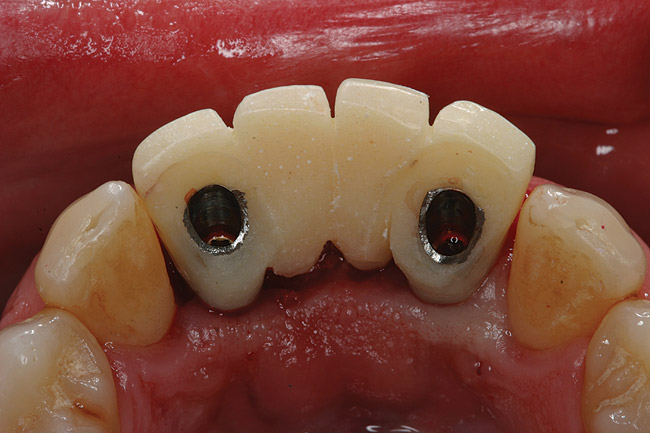

Figure 5  Tapered implants with conical transgingival abutments and temporary cylinders in place.

Figure 5